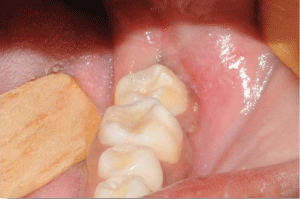

The transplanted tooth and the gums were healthy 1 year after the surgery. Moreover, the patient did not complain and said she was satisfied with the result (Figure 12 and Figure 13).

Figures 12: One year after the surgery. The transplanted tooth and the gum were healthy.